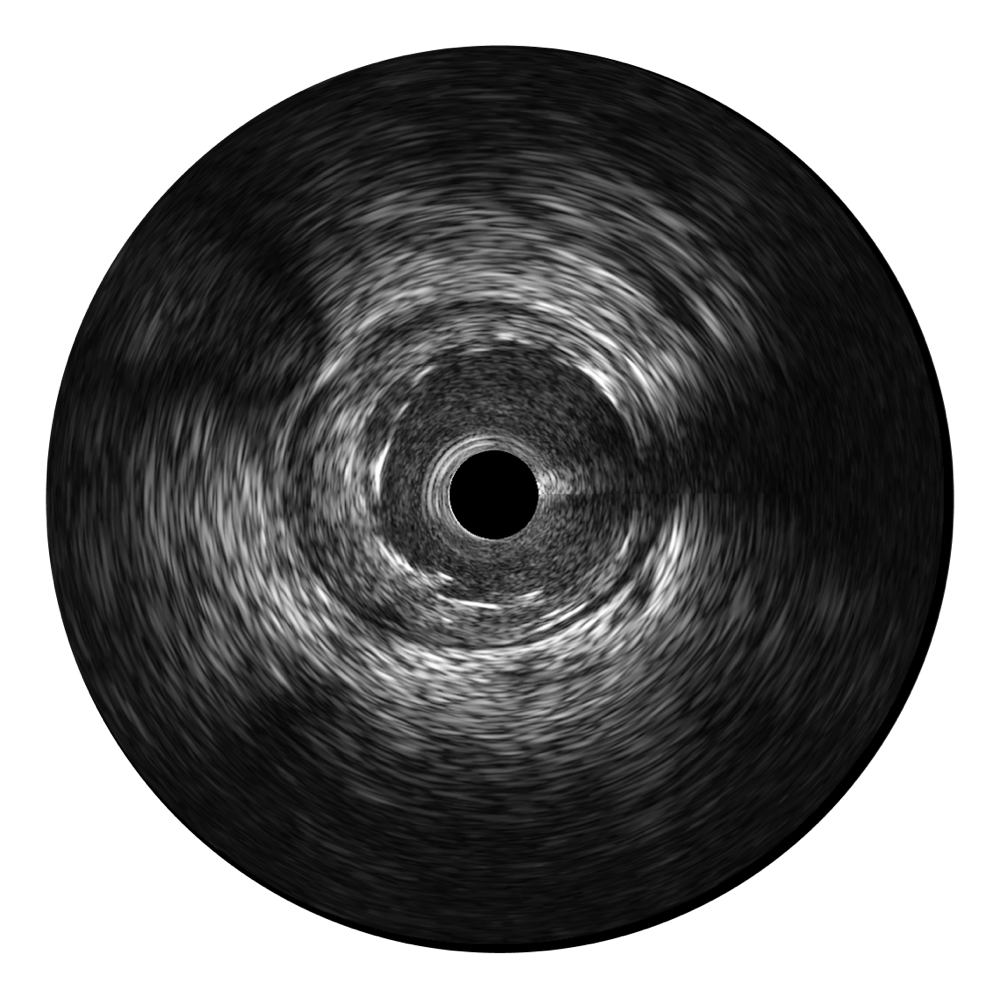

milan米兰宽频IVUS图像

传统IVUS图像

对比传统IVUS导管成像,milan米兰宽频IVUS图像的近场支架梁显影更细腻,远场中膜外血管仍清晰可辨,兼顾远中近,兼顾分辨力与穿透深度